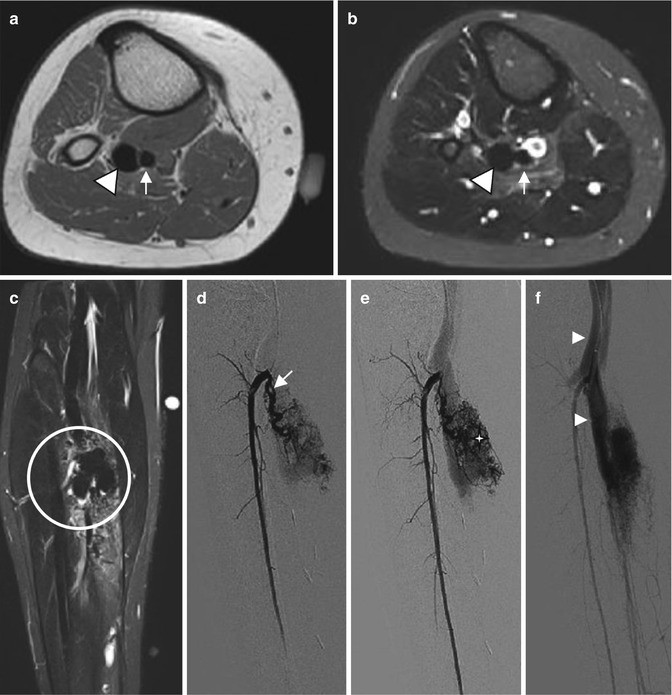

Complex arteriovenous malformation affecting the calf in a 15-year-old woman. (a) Axial T1-weighted MR image. (b) Axial T2-weighted MR image with fat suppression. (c) Coronal T2-weighted MR image with fat suppression. (d–f) Conventional angiographic images acquired from early arterial phase to venous phase. (a, b) Signal voids in the high flow vessels can be depicted on both T1-weighted and T2-weighted MR images, including the feeding artery (arrow) and arterialized draining vein (arrowhead). (c) Coronal T2-weighted MR image reveals the nidus (circle). (d–f) Arteriogram acquired demonstrates a slightly enlarged tortuous artery (arrow) during the early arterial phase, the nidus (star) on late arterial phase, and then enlarged draining veins (arrowheads)